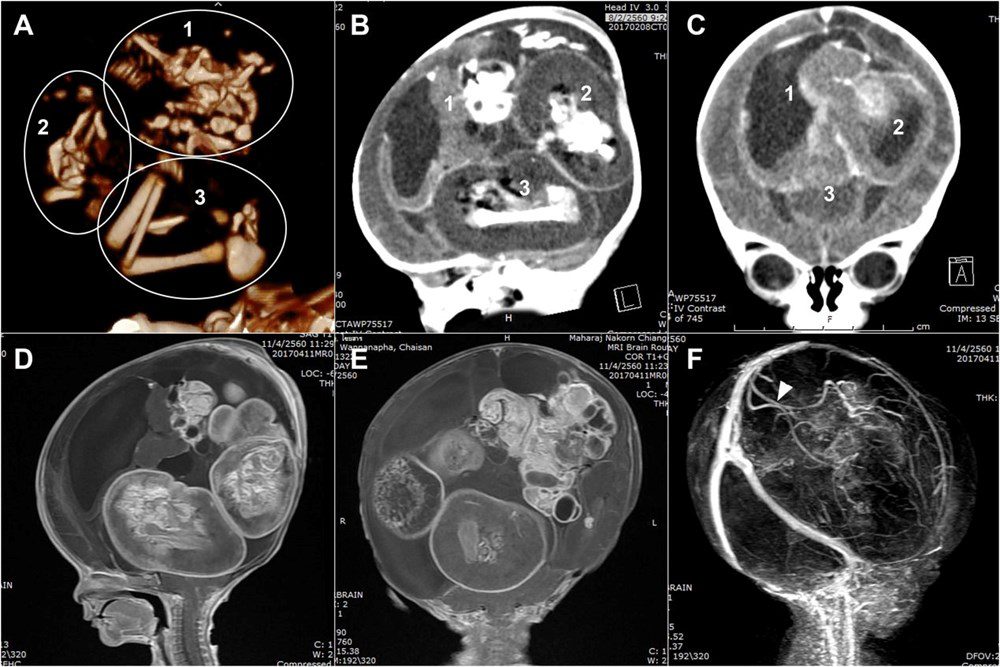

Yeni bir araştırmaya göre, Çin’de doktorlar bir yaşındaki bir çocuğun beyninde ‘doğmamış ikizinin fetüsünü’ buldu. Neurology dergisinde yayınlanan çalışmada, çocuğun motor fonksiyonlarında sorunlar yaşaması ve kafasının büyümesi üzerine ebeveynleri tarafından hastaneye getirildiği ortaya çıktı. Şangay’daki doktorlar, doğmamış ikizin fetüsünün çocuğun beyninde geliştiğini tespit etti. Çalışmanın yazarları, “Motor becerilerinde gecikmesi ve genişlemiş baş çevresi olan 1 yaşındaki bir kız çocuğunda malforme olmuş monokoryonik diamniyotik ikiz olan intraventriküler fetüs içinde fetüs (fetus-in-fetu) tespit edildi.” denildi.

Parazit ikiz olarak da adlandırılan fetüs içinde fetüs, ikizlerin rahimde yapışık olması, ancak yalnızca birinin gelişmeye devam etmesi durumunda ortaya çıkıyor. Çalışmada, genom dizilimi sonrasında fetüsün çocuğun ikizi olduğunun tespit edildiği de belirtildi.

Bununla birlikte fetüs içinde fetüs vakaları ikiz gebeliğin çok erken aşamalarında, döllenmiş bir yumurta tarafından oluşturulan ve blastosist olarak adlandırılan bölünen hücre kümesinin düzgün bir şekilde ayrılamamasıyla meydana geliyor. Ardından embriyolardan biri diğeri tarafından çevreleniyor.

Diğer ikizin çoğalan hücreleri tarafından sarılan öteki fetüs gelişemiyor, ancak kan desteği aldığı için “canlı” kalıyor.  Çalışmada, “Yapışık parçalar ana fetüsün ön beynine dönüşüyor ve nöral plak katlanması sırasında diğer embriyoyu sarıyor.” ifadeleri kullanıldı.